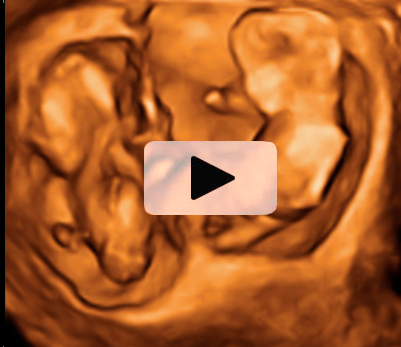

Ecografía en 2D y 3D de gemelos de 11 semanas en planos diferentes

Imágen en dos dimensiones de un embarazo gemelar. El ecografista toma una "porción de imagen" (rectángulos) y luego otro corte o plano diferente (cuadrado), que corresponde a imágenes en 2D y 3D. Podemos observar con gran nitidez a los gemelos en dos bolsas independientes, así como las placentas que los alimentan. La membrana de separación entre ambos hermanos es muy gruesa. El punto central de color que aparece en las ecografías en dos dimensiones (2D) corresponde con la membrana de separación de los gemelos. La imagen en 3D lo confirma sin género de duda.